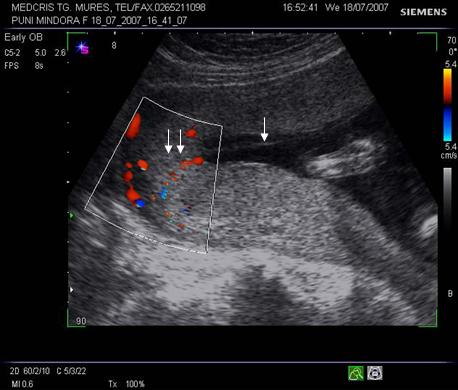

Fig.nr 46 . Separatie

placentara (trei sageti) in continuarea membranei despartitoare amniotice (cu o

sageata) , cu semnal Doppler la ambele placentatii